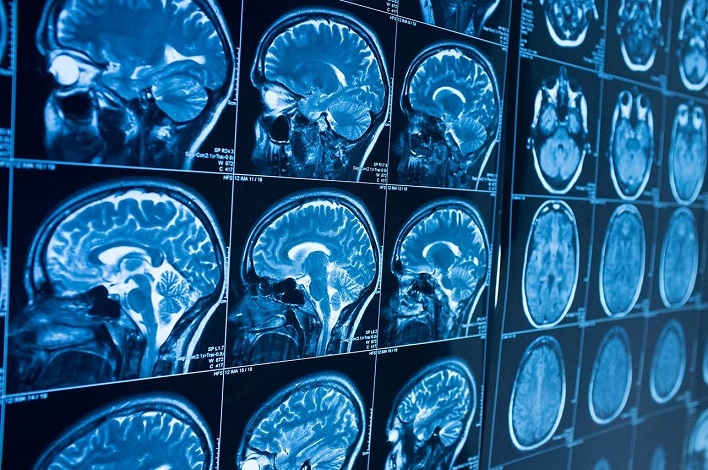

В среду стало известно о феноменальном случае выживания пожилой женщины, которая прожила 80 лет с иглой в мозгу. Невероятное открытие произошло во время компьютерной томографии. Об этом сообщает Science Alert.

Фото из открытых источников

Врачи уверены, что женщина стала жертвой неудачного детоубийства, совершенного ее родителями. Удивительно, но медики решили не пытаться извлечь иглу из ее мозга, опасаясь ухудшить ее состояние.

«Игла вошла в ее левую теменную долю, но это не возымело желаемого эффекта – девочка выжила», - сообщили в местном департаменте здравоохранения.

Интересно, что игла находилась в левой теменной доле мозга женщины, но, несмотря на это, она никогда не испытывала головные боли или другие серьезные проблемы из-за этой травмы. Ее состояние контролируется лечащим врачом.